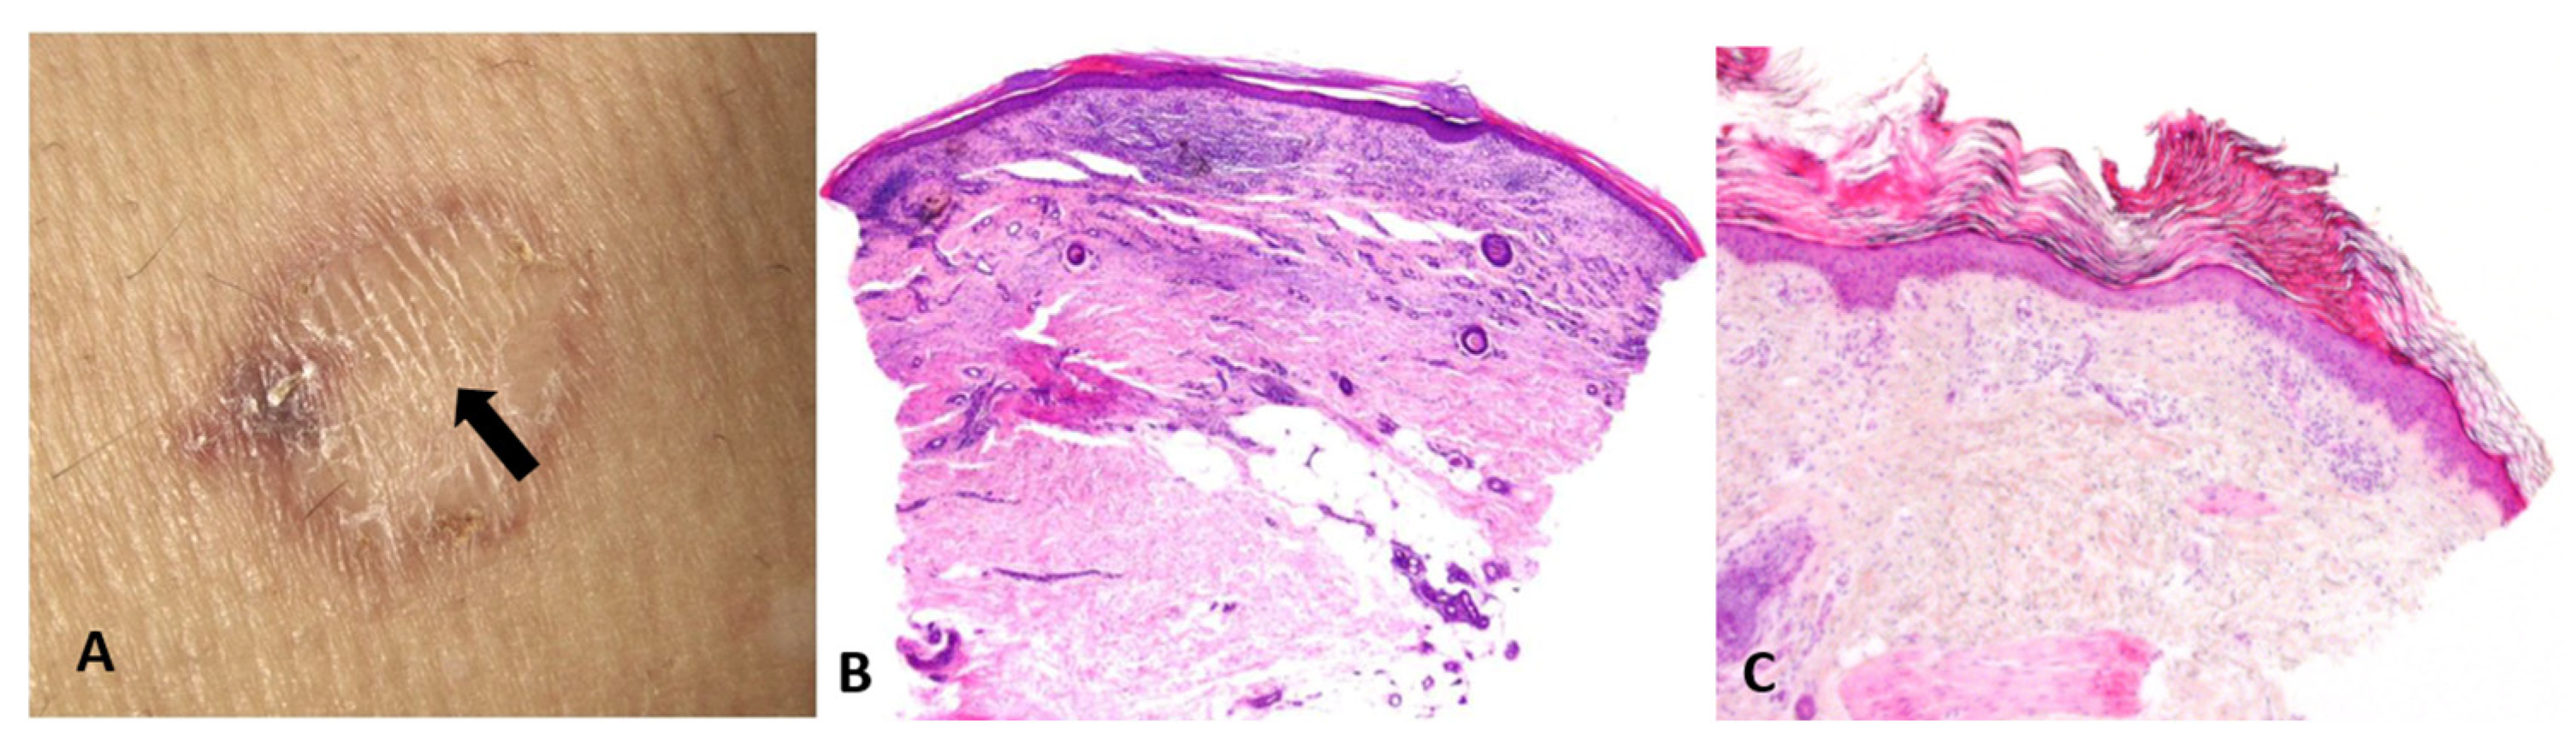

- Artifacts and actions matter: Biopsy site selection, technique (punch vs. shave vs. excision), depth, and handling are not mere logistics; they are integral to reasoning itself—manipulative abduction. Actions generate the very data required for the next abductive step. For example, a common sampling error in daily dermatologic practice is taking a biopsy from the central area of porokeratosis (Figure 5).

Figure 5. (A) Biopsy from the regressing center of a porokeratosis lesion (arrow). (B) Nondiagnostic pathology, showing lichenoid infiltrate, fibrosis, and angiogenesis. (C) Biopsy from the elevated border of a porokeratosis lesion, revealing the characteristic cornoid lamella—a column of parakeratotic cells that represents the hallmark of the condition.